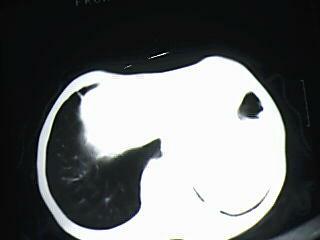

以下是引用xiaomeng在2009-5-4 16:46:00的发言:[br]肺癌

以下是引用杀毒软件在2009-5-4 17:57:00的发言:[br]块影+不张=肺癌

以下是引用随光逐影在2009-5-4 19:15:00的发言:[br]1)考虑左肺周围型肺癌。2)左肺感染性病变并节段性肺不张。